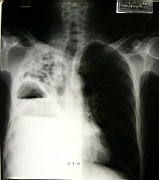

This patient has both a pulmonary abscess and an empyema at the same time! |

Lateral view, same patient |